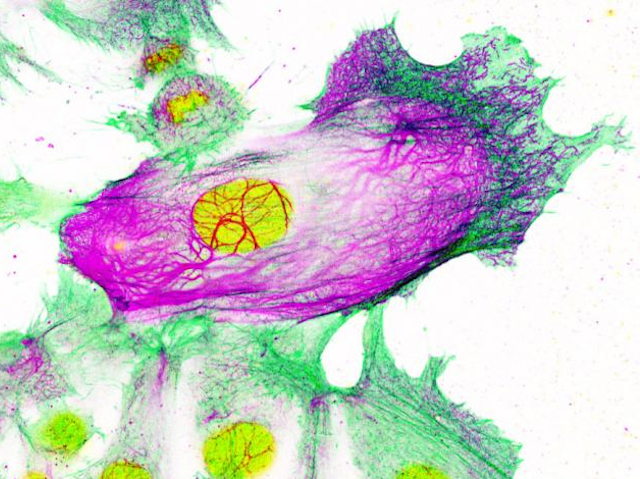

For the most common type of breast cancer, treatment often involves aromatase inhibitors (AIs), drugs which block oestrogen production. While initially effective, cancer can return, and when it does, the cancerous cells may be resistant to AIs, and may have spread by metastasis. Recent research suggests this could be because treatment with AIs causes epigenetic changes, modifications around DNA that alter how genes are transcribed, leading to an increase in keratin-80 (pictured, in purple, in an AI-resistant cancer cell surrounded by non-resistant cells, with cell nuclei in yellow). Related to keratins in hair and nails, this scaffolding protein makes cells stiffer, which could help them move and invade other tissues more easily during metastasis. While further studies are needed, these results suggest a link between resistance to AIs and increased metastatic potential, so targeting the resistance mechanism could be an effective route towards preventing future metastasis in breast cancer patients.